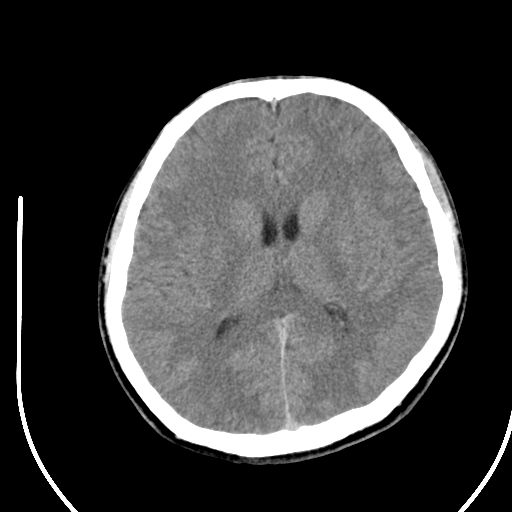

标题: CT28158:男,27Y。头痛数月,左顶叶血管瘤。 [打印本页]

标题: CT28158:男,27Y。头痛数月,左顶叶血管瘤。

海绵状血管瘤

考虑左顶叶海绵状血管瘤,建议mr检查。